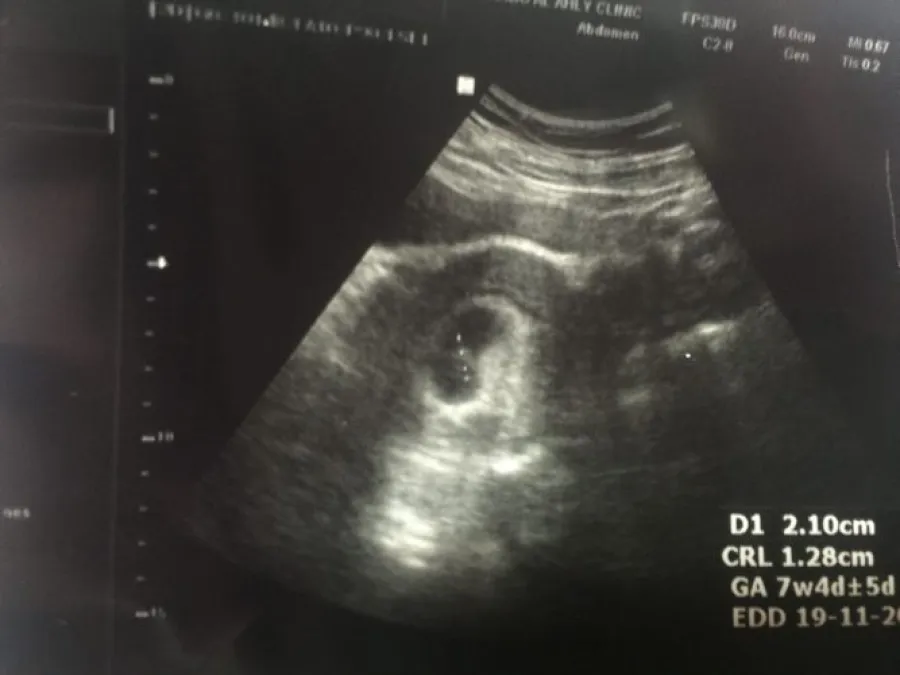

- فيمر الجنين في الشهر الثاني من الحمل برحم الأم بالعديد من التغيرات، ومنها الأسبوع الخامس والسادس؛ حيث يصل طول الجنين إلى 1.15 سم، ويبدأ القلب في النبض، وتتطور الدورة الدموية والبراعم المسؤولة عن الأطراف.

- أما الأسبوع السابع والثامن، فيصل طوله إلى 1.30 سم، يتشكل القلب وتتكون الأطراف وينحني الذراعان عند المرفقين، وتبدأ الأذنان خارجياً والعينان والجفون والكبد والشفة العليا في التكوين. أما هوية الجنس فلا نستطيع معرفتها في هذا الشهر.